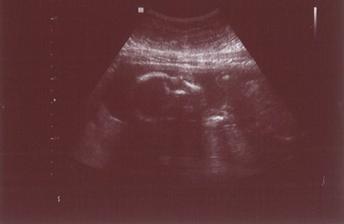

23/2.. tááák a máme za sebou genetický UTZ... máme 7,1 cm (takže jsem podle UTZ stále o 4 dny větší), máme dvě ručičky, dvě nožičky, na každé končetině 5 prstíků... krásnou páteř, zárodky zoubků, žaludek i močový měchýř... přítomna je dle pana doktora "výstavní" nosní kůstka a NT hodnota je 0,9... pravděpodobnost Downova syndromu je 1:4100 (prý nádherný výsledek)... jsem šťastná jako blecha... jenom mimís nás trošku zlobil, porád byl v takovém polospánku... pan doktor do něj šťouchal, já kašlala o sto šest, ale náš pohodář se ani nehnul.. a pan doktor potřeboval, aby se pootočil.. no nakonec sebou začal vztekle škubat, na chvilku se pootočil a zase upadl do spánku... takže žádné přemety, žádné artistické výkony, prostě je to pěknej povaleč.. ale už teďka ho šíleně miluju, je můj a dělá mi jenom samou radost (doufám, že mu to spinkání vydrží i až bude na světě!!!!) Další kontrola včetně tripl testu bude 20/3/09... uffff, zase je to tak za dlouho!!!!